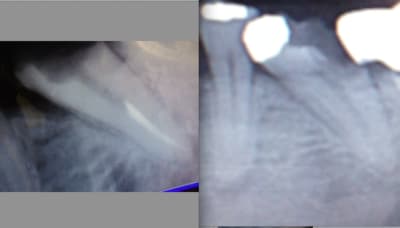

> A la radio ta racine discale est double,´donc deux canaux sauf si ils se

> rejoignent dans le tiers apical; tu peux aussi avoir un gros canal commun au

> début puis une bifurcation a la toute fin. Mais ce qu il y a de casi s^ur, c est

> qu il y a 2 canaux mésiaux. ( si les 8 % sont exacts, j ai fait beaucoup de faux

en lisant ton lynchage en regle sur le forum :-), j'ai re regardé les radios, et j'avais oublié de précisé qu'il y a un petit risque que ta douleur vienne d'un stripping de la paroi distale de ta racine mésiale (tu suis? ;-) ) réalisée avec tes limes. Es tu bien su^r que tes cones de papiers étaient parfaitement secs avant d'obturer, ou y avait-il un une humidité à mi hauteur de ton cone de papier?